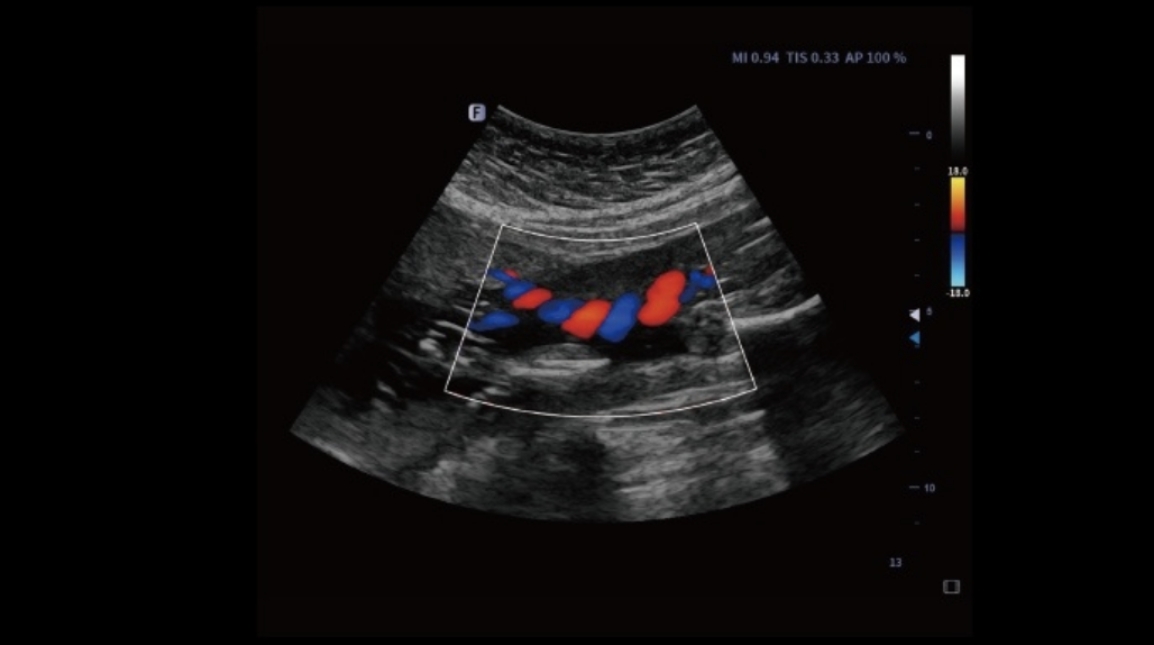

Auto Volume Flow

Mierzenie powierzchni naczynia krwionośnego, prędkość przepływu krwi może być automatycznie mierzona przez spektrum, a wyniki objętości przepływu krwi zostaną wyświetlone.

Obrazy kliniczne